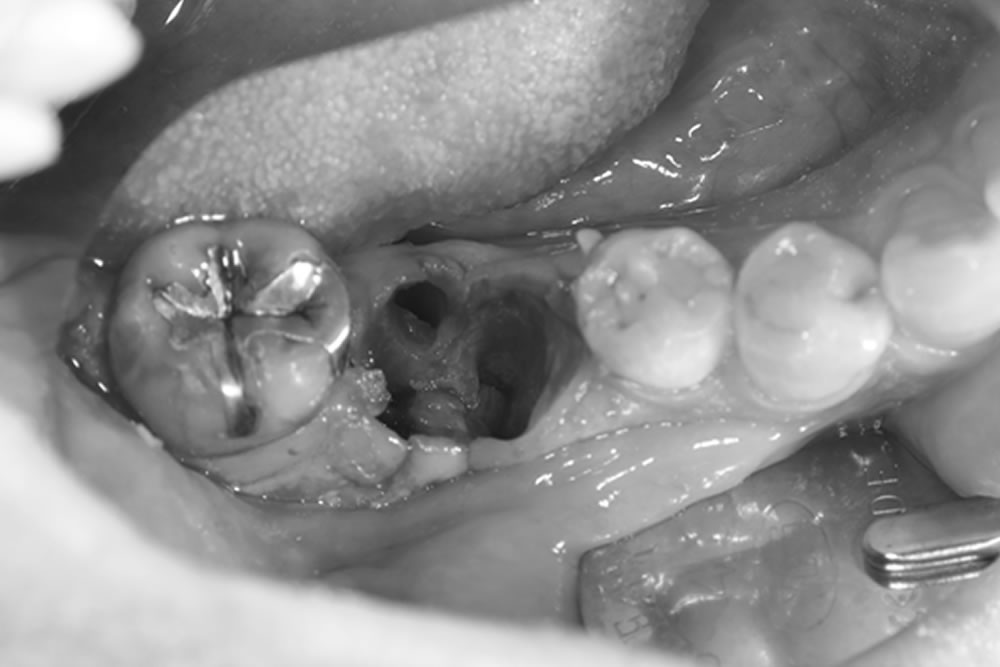

インプラント手術の実施

上部構造の装着・治療完了

3ヶ月後に二次オペを行い、その後の歯肉の状態を確認したところ、周囲歯肉に炎症は認められませんでした。